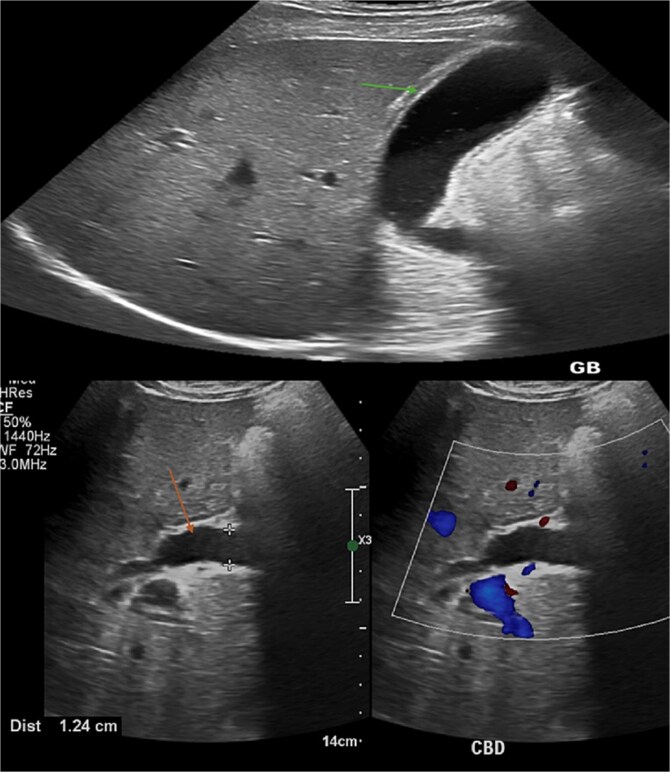

On presentation, the patient was oriented, stable, and comfortable. On physical examination, the patient had obvious jaundice, but no abdominal tenderness or hepatosplenomegaly. An ultrasonography revealed significant dilatation of the common bile duct (orange arrow) measuring 12.4 mm, without obvious ductal stones. The gallbladder also showed distension and edematous wall (green arrow) resembling features of cholecystitis, but no sizable stones could be detected. (Fig. 1).